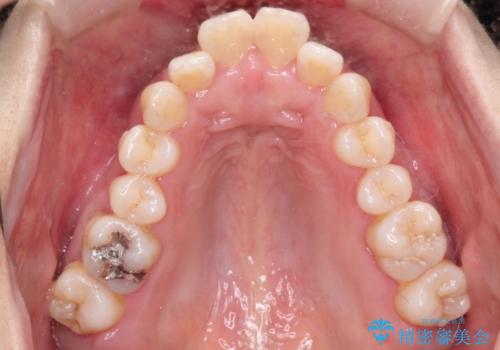

- 出っ歯がきになるとのことで来院されました。

上顎の前歯は前方に傾斜しており、下あごの前歯にもガタガタがありました。

上下左右の小臼歯を合計4本抜歯して矯正することとしました。

矯正を開始する前から歯肉退縮があり、悪化しないように注意しながら矯正治療を行いました。